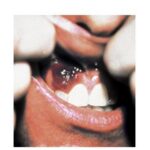

disease onset and have a tendency for rapid progression. In contrast to other variants of KS, the initial lesions in AIDS patients frequently develop on the face, especially on the nose, eyelids, and ears, and on the trunk, where the lesions follow the relaxed skin tension lines . If untreated, disseminated AIDS-KS lesions may coalesce to form large plaques involving large areas of the face, the trunk, or extremities and lead to functional impairments. The oral mucosa is frequently involved and represents the presenting site in 10 percent to 15 percent of AIDS KS . Involvement of the pharynx is not uncommon and may result in difficulty eating, speaking, and breathing.

Involvement of extra-cutaneous sites occurs more rapidly and more dramatically in patients with AIDS KS than in those with classic KS. In addition to the oral mucosa, KS lesions are most frequently found in lymph nodes, the gastrointestinal tract, and the lungs. Although gastrointestinal KS is usually found when cutaneous lesions are present, exclusive gastrointestinal involvement is possible. The stomach and duodenum represent predilection sites and KS lesions there can cause clinical symptoms such as bleeding and ileus. Although visible on gastroscopy, such lesions are underdiagnosed histologically because they are located in the submucosa and may escape the biopsy forceps. Pulmonary KS can cause respiratory symptoms such as bronchospasm, coughing, and progressive respiratory insufficiency.62 Bronchoscopy with transbronchial biopsy is most appropriate for the diagnosis of pulmonary KS.